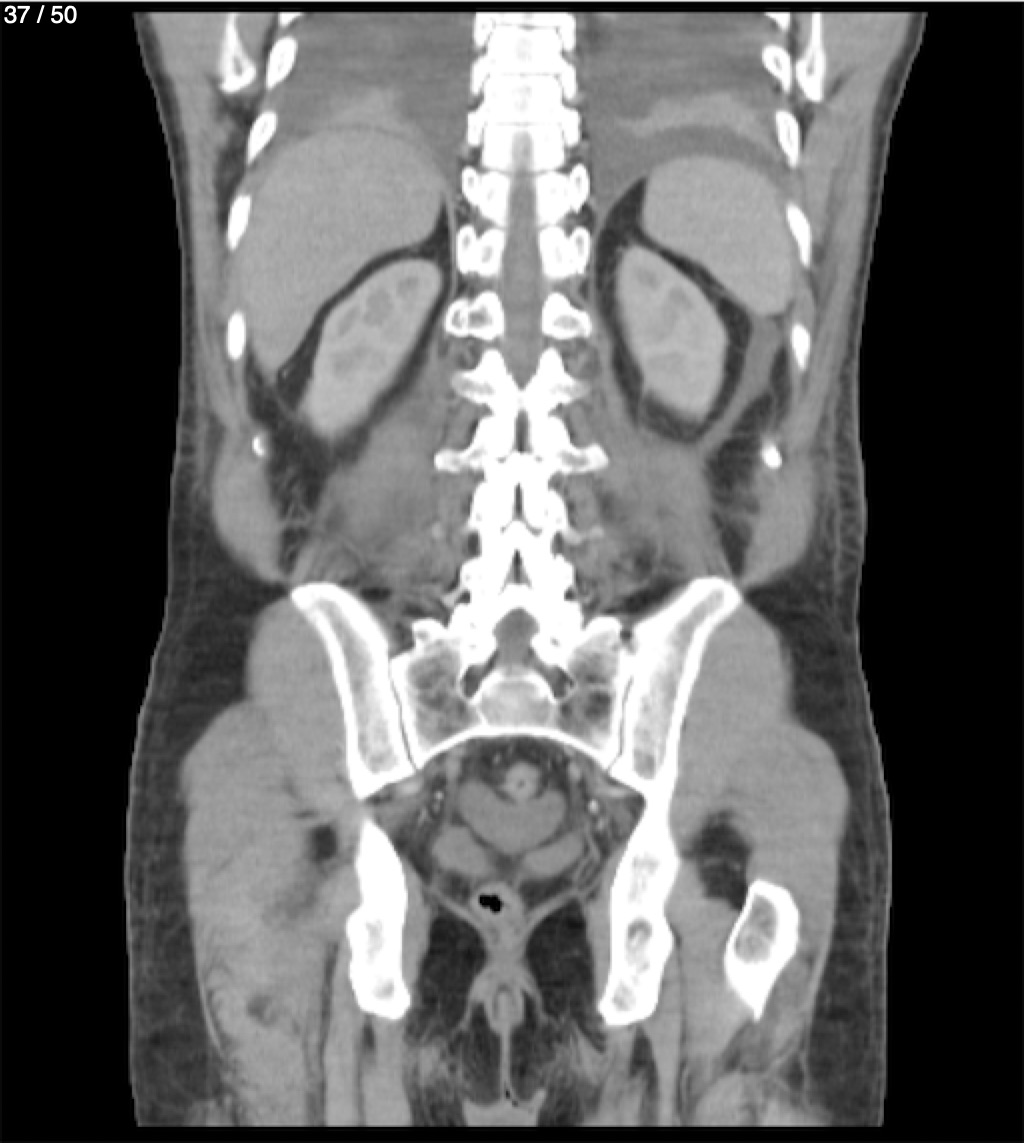

Alonso Victorio Ruiz 62A - T.C Abdomen Syc